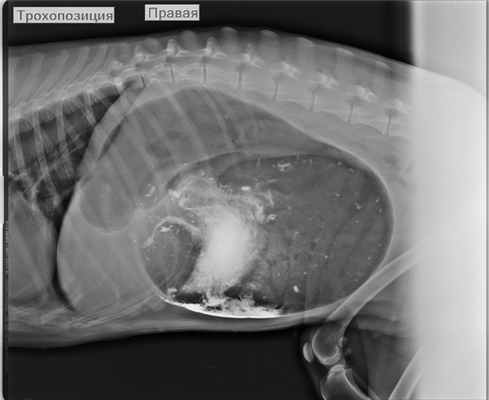

Перекрут желудка.

На рентгенограмме визуализируется расширенный желудок с контрастным веществом (сульфат бария).

Ось желудка изменена, эвакуация контрастного вещества отсутствует.